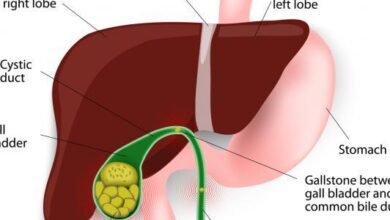

هناك العديد من الأسباب التي تؤدّي إلى زيادة نسبة الدهون في الكبد، نذكر منها:

- السمنة الزائدة للجسم خاصةً في الجزء العلوي (منطقة البطن).

- إصابة الجسم بمرض السكري.

- الإدمان على تناول المشروبات الروحية.

- تناول بعض الأدوية بكثرة، مثل حبوب منع الحمل، وبعض أدوية تنظيم دقات القلب.

- النظام الغذائي الذي يتناوله الشخص.

- قلة ممارسة الرياضة أو المشي.